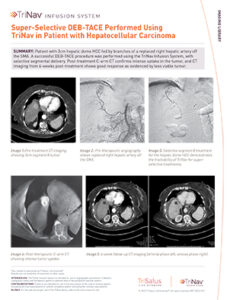

Super-Selective DEB-TACE Performed Using TriNav in Patient with HCC